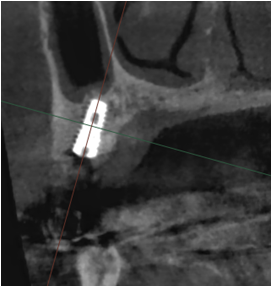

뼈이식 임플란트는 잇몸뼈의 길이나 두께가 부족하거나 잇몸뼈 흡수가 심한 경우 잇몸뼈의 재생을 도와주어 임플란트 식립이 가능하도록 하는 치료입니다.

임플란트 환자 중 치조골이 부족한 경우에 해당될 때 인공 뼈 이식을 통해 부족한 뼈를 보충하고 임플란트 식립을 진행합니다.

임플란트 치료가 필요하지만, 잇몸뼈의 조건이 좋지 않을 때 진행하게 됩니다.

뼈의 밀도가 치밀하고 단단할수록 임플란트의 성공률은 높아집니다.